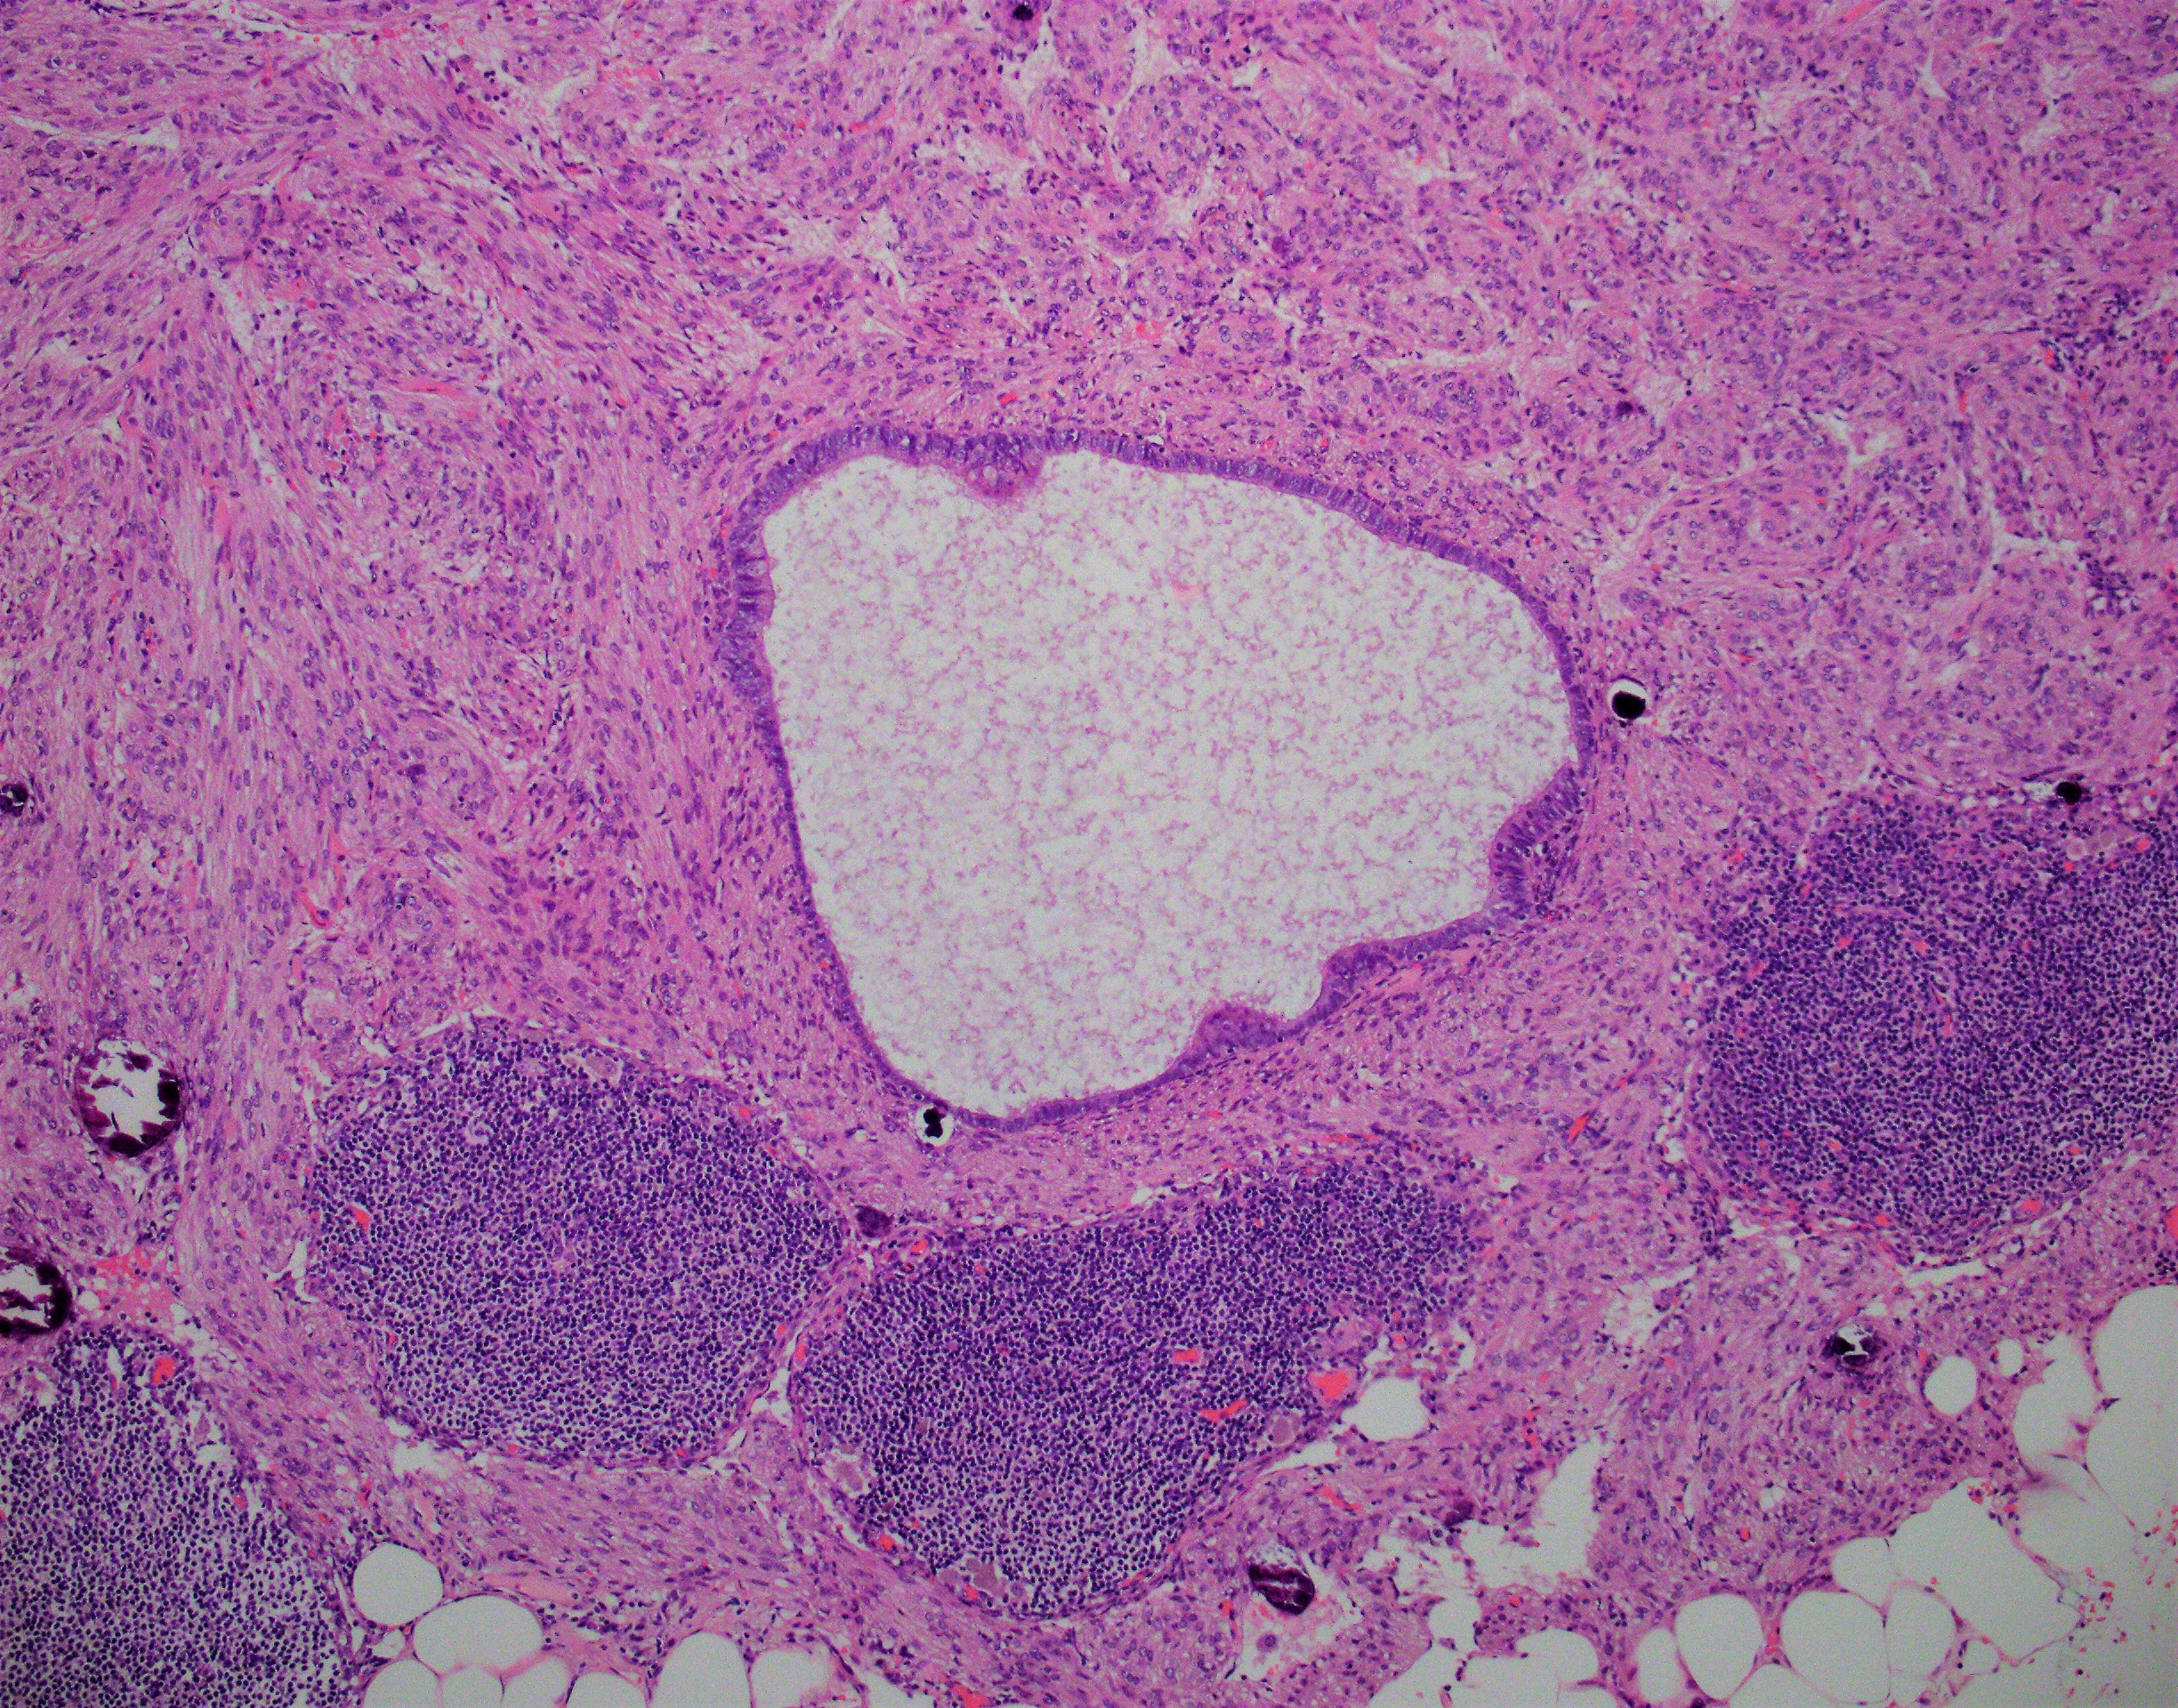

A 50 year old woman presented with abdominal pain. Examination of a pelvic sidewall lesion revealed cystic tissue lined by ciliated epithelium with underlying fascicles of spindle cells positive for SMA and HMB-45. Similar spindle cell aggregates were found in a lymph node.

C: The correct answer is lymphangioleiomyomatosis (LAM) with endosalpingiosis.

LAM usually involves the lymphatic system, lungs, and kidneys. However, as in this case, it can be an isolated finding. Manifestations include overgrowth of smooth muscle-like cells in the lungs resulting in cyst formation leading to sequelae such as pneumothorax. Overgrowth of the cells in lymphatic vessels results in formation of lymphangiomas. Renal involvement usually occurs in the form of angiomyolipomas. Lymph node involvement by LAM is a less commonly documented occurrence that can be mistaken for metastasis.